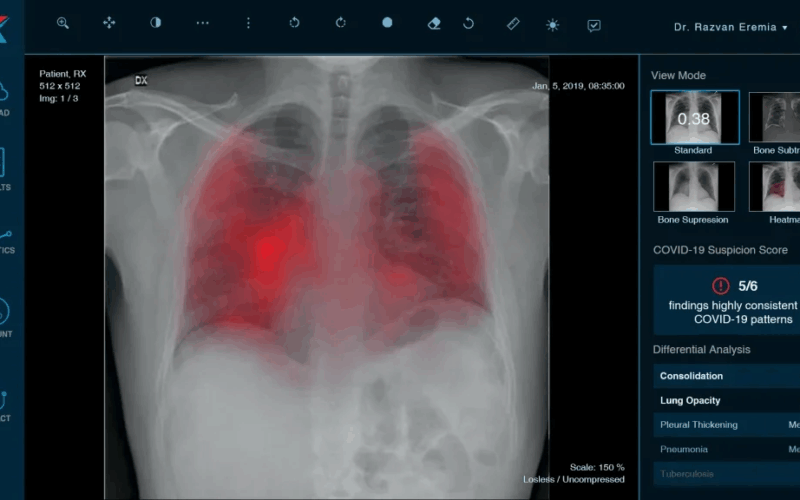

Film versus realitate: Inteligența Artificială, de la computere malefice la instrumentul salvator de vieți din medicina de azi. Dr. Dragoș Cuzino: „În medicină, AI-ul nu are autonomie și nu ia decizii pe cont propriu”